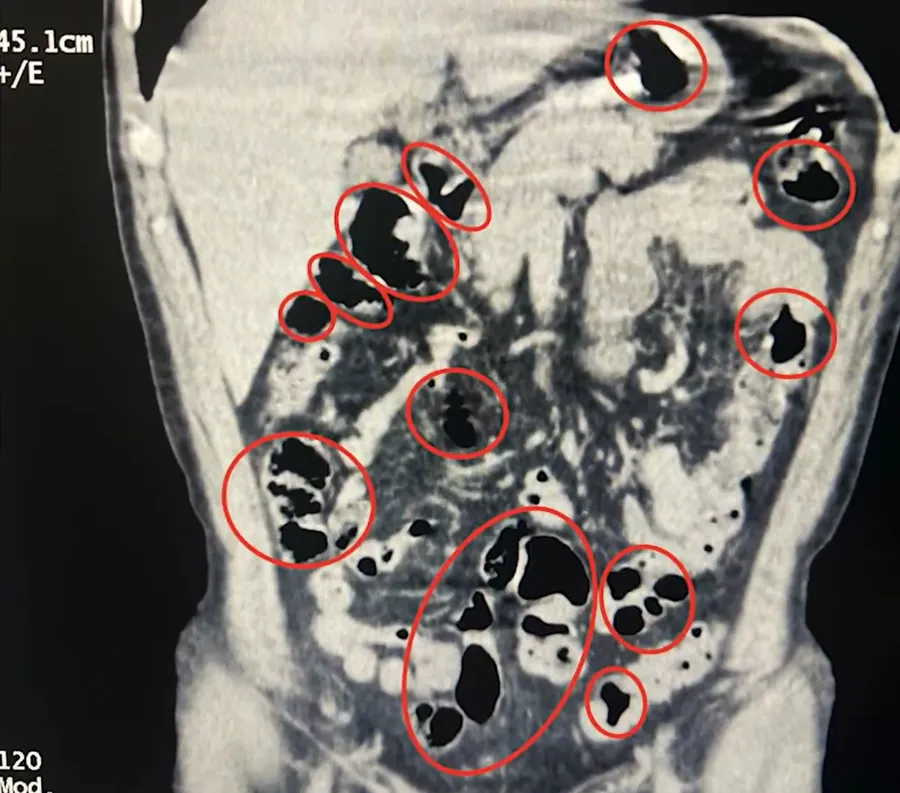

İkinci operasyon ise yine Tatvan’da bir yolcu otobüsünde yapıldı. Yolcu olarak bulunan yabancı uyruklu 2 şahıs, durumlarından şüphelenilmesi üzerine gözaltına alındı. Tatvan Devlet Hastanesinde yapılan röntgen ve tomografi incelemelerinde, şahısların mide ve bağırsaklarında çok sayıda yabancı cisim tespit edildi.

Tıbbi müdahale sonucunda, zanlıların yuttuğu 14 kapsül ve üzerlerinde bulunan 36 kapsül ile birlikte toplam 50 kapsül, 385 gram metamfetamin ele geçirildi.